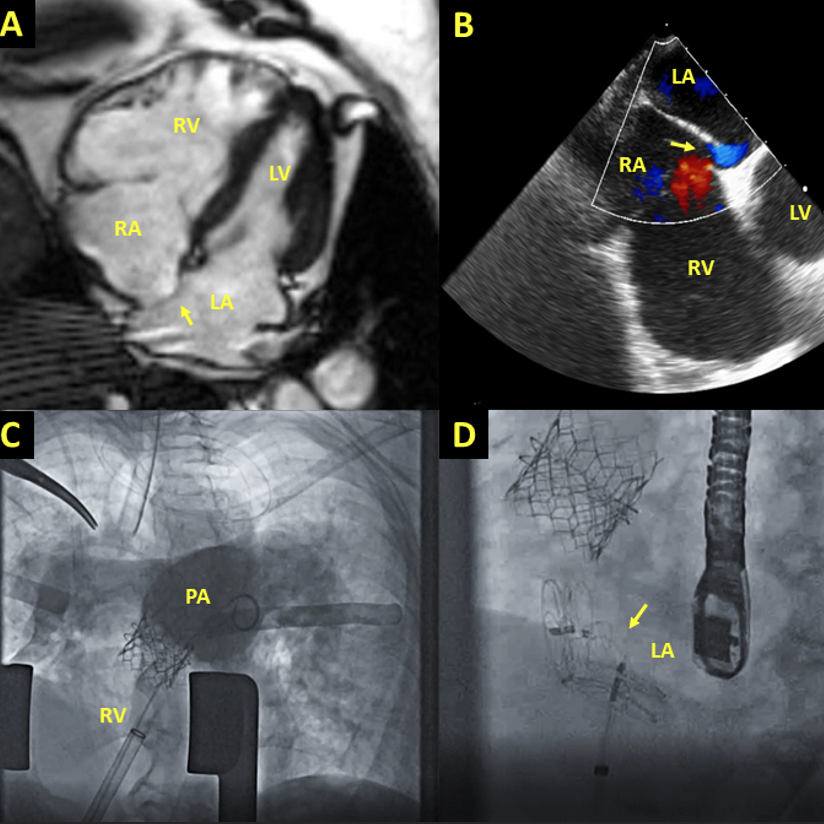

Videoclips in "PFO Closure after Pulmonary Valve Intervention in Patients with Hypoxemia Due to Right-to-Left Intracardiac Shunt" by Suhas Babu Zhihao Zhu Rahul Singh Valeria Duarte MD MPH C. Huie Lin MD, PhD Drs. Chavez, Li, El Nihum & MacGillivray #DeBakeyCVJournal doi.org/10.14797/mdcvj…

Always a joy talking about cardiology and #ACHD. Thanks so much to mentors and programs! C. Huie Lin MD, PhD Valeria Duarte MD MPH Melina Awar, MD Houston Methodist IM Residency Houston Methodist Cardiovascular Fellowships DeBakey CV Education - World Class CV Training #ACC2023

As the population of patients with #ACHD grows, the potential need for transcatheter interventions increases. "Percutaneous Structural Interventions in Adult Congenital Heart Disease" by Rody Bou Chaaya Zhihao Zhu Valeria Duarte MD MPH C. Huie Lin MD, PhD #DeBakeyCVJournal doi.org/10.14797/mdcvj…